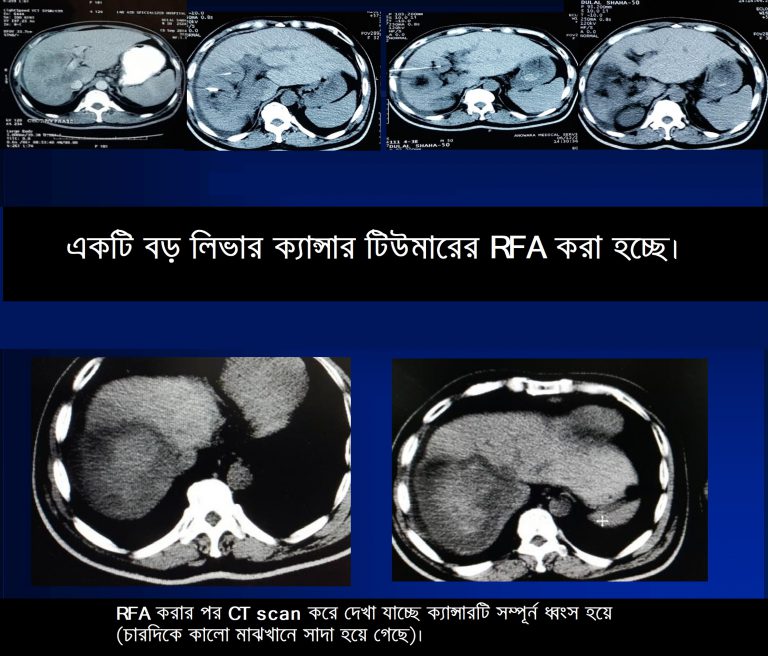

২। RFA (রেডিও ফ্রিকোয়েন্সি এব্লেশন)

২.RFA (রেডিও ফ্রিকোয়েন্সি এব্লেশন)ঃ এই পদ্ধতি ব্যবহারের মাধ্যমে ৫-৬ সেঃমিঃ লিভার টিউমার কে সম্পূন ধ্বংস করা সম্ভন হয় অথচ আশেপাশের সুস্থ কোষের কোন ক্ষতি হয় না। এ পদ্ধতির সফলতার হার ৮৫%-৯৫%। এ কারনে ৫-৬ সেঃমিঃ লিভার ক্যান্সার এর চিকিৎসা হিসেবে সারা বিশ্বে আর এফ এ (RFA) সব চেয়ে বেশি সমাদূত। এর পার্শ্ব প্রতিক্রিয়াও খুবই কম।